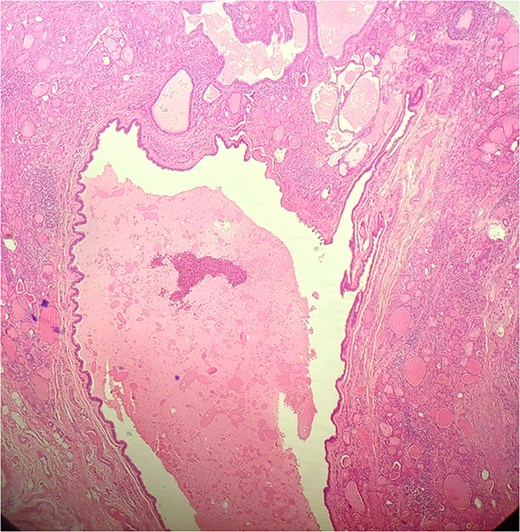

A 47-year-old woman with unremarkable medical history, presented with a 2 months history of neck mass along the midline. Physical examination revealed a 6 cm mobile, thyroid nodule without compressive symptoms. There was no associated erythema, fluctuance, tenderness or adhesion to adjacent structures. There was also no associated cervical lymphadenopathy. The rest of the physical exam was unremarkable. Laboratory tests including TSH, FT3, and FT4 revealed normal levels. On cervical ultrasound, there were a 62 mm left toto-lobar nodule classified as EU-TIRADS3, and an 11 mm right nodule, also classified as EU-TIRADS3. Fine-needle aspiration cytology concluded to a benign lesion classified as BETHESDA II. The patient reported respiratory discomfort in the supine position, leading to the indication for a lobectomy. Gross examination of the specimen revealed a toto-lobular nodule with a colloid appearance. It was well-circumscribed by a thin and regular fibrous capsule. The nodule measured 4 × 6 cm and exhibited areas of fibrous, whitish remodeling, as well as hemorrhagic and cystic changes. On microscopic examination, the nodule corresponded to a macro vesicular adenoma altered by fibrosis and hemorrhage. It was surrounded by a thin, regular, and intact fibrous capsule. However, at the periphery of the nodule, adjacent to the thyroid pseudo capsule, a 1.2 cm cystic ductal structure was observed. It showed pseudostratified ciliated columnar and squamous epithelial lining associated with thyroid follicles in the surrounding stroma (Figs 1 and 2). These thyroid follicles were bland with no papillary nuclear atypia or invasion (Fig. 3). The cyst was filled with a thin eosinophilic material (Fig. 4) Lymphocytic thyroiditis of mild severity was identified in the rest of the thyroid tissue. Based on these findings, the diagnosis of macro vesicular thyroid adenoma with ITTGDC and lymphocytic thyroiditis was made. After the surgery, the patient developed temporary dysphonia.